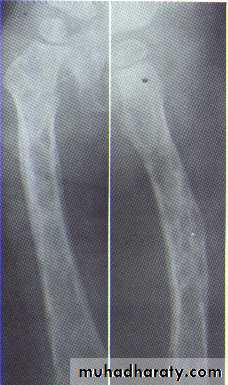

• Multiple radiolucent foci seen in the skull & long bone of the skeleton, lesion in the skull give appearance of geographic map , with skull enlargement .